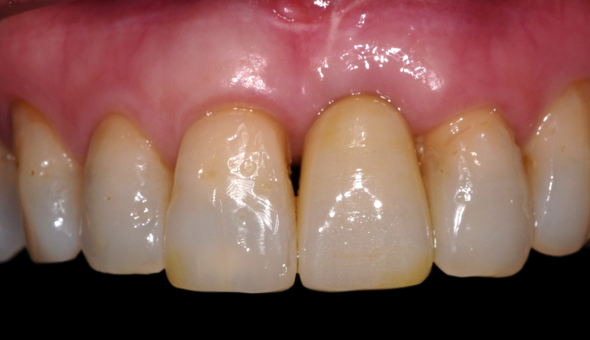

최종 완성

잇몸이식의 효과로 오른쪽 위 앞니 뿌리도 덮어져 시술 전보다 앞니의 외형이 많이 좋아졌습니다.

기존 치아사이 공간도 오른쪽 윗니 치아에 레진이라는 치과 재료를 통해 치아 모양을 예쁘게 만들어 주었고

임플란트 치아 보철도 심미적인 균형을 맞추어 치료를 완료했습니다.

자세하게 보지 않으면 모를 정도로 차이가 미세해서 잇몸이식 없이 치료를 완료하였습니다.